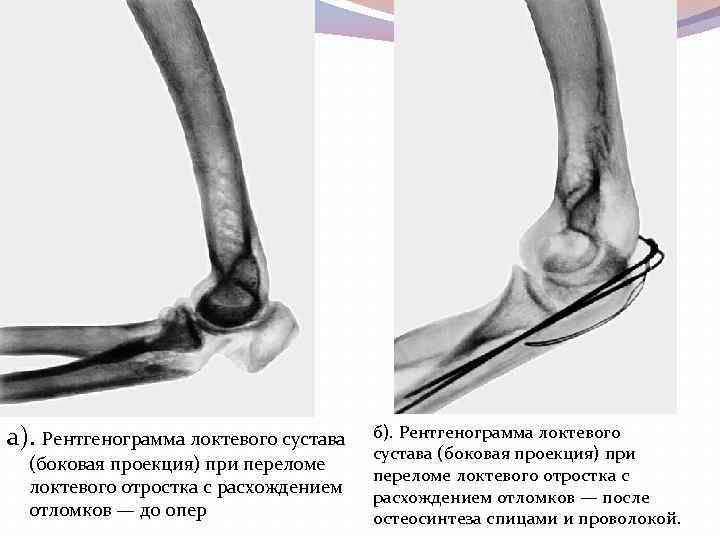

Переломы локтевого отростка чаще возникают в результате действия прямой механической силы. Пальпация и давление на отросток вызывают усиление боли. При переломе с расхождением отломков между ними отчетливо пальпируется поперечно расположенная щель или западение. Ротационные движения предплечья свободны и безболезненны. Пассивное разгибание предплечья происходит под тяжестью предплечья и кисти. Активное сгибание в Л. с. сопровождается усилением болей. Лечение при переломах без расхождения отломков заключается в наложении на 3— 4 нед. тыльной гипсовой лонгеты в положении сгибания Л. с. под углом 90— 1 10°. При переломах с расхождением отломков (рис. а) лечение оперативное (рис. б).

а). Рентгенограмма локтевого сустава (боковая проекция) при переломе локтевого отростка с расхождением отломков — до опер б). Рентгенограмма локтевого сустава (боковая проекция) при переломе локтевого отростка с расхождением отломков — после остеосинтеза спицами и проволокой.